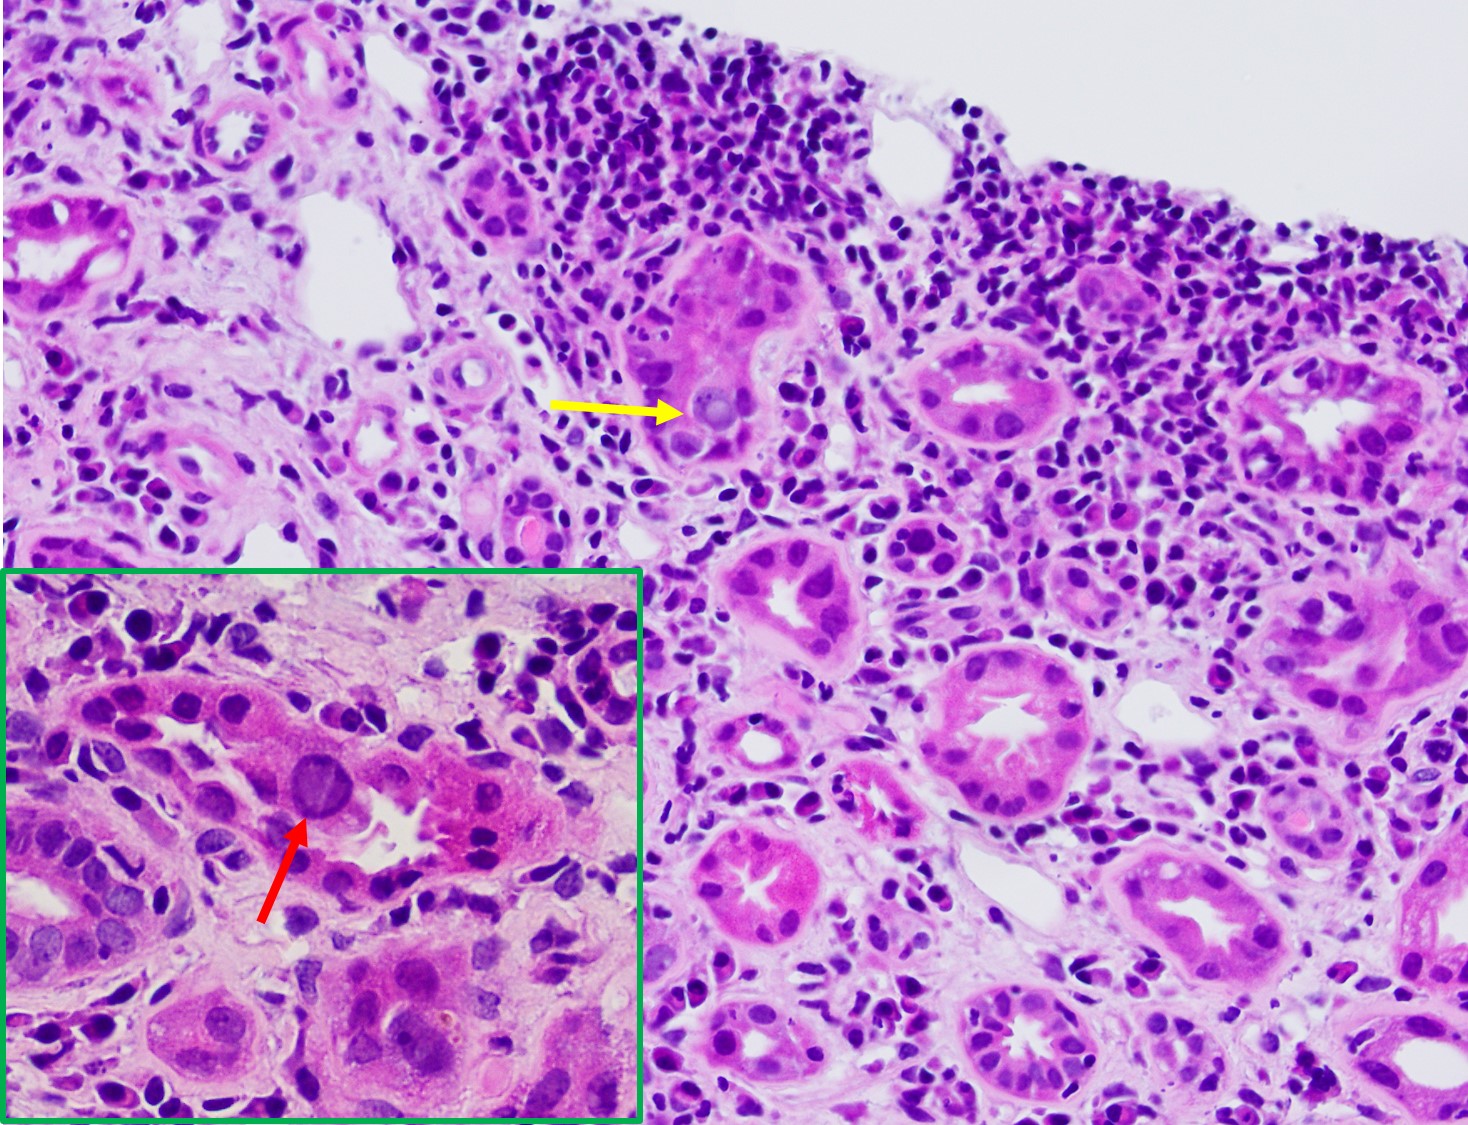

It is not always easy of straightforward to distinguish BK nephropathy from acute rejection, and very difficult to diagnose a coexisting lesion including both of them. T cell-mediated rejection shares similar histopathologic features with BK nephropathy, such as focal and brisk interstitial inflammation and tubulitis (shown in Fig. 1). However, typical viral cytopathic changes are more common in BK nephropathy, such as nuclear enlargement and intranuclear infusion (Fig. 2, yellow arrow) and features resenbling so called "decoy cells" in urine cytology (Fig. 2, red arrow). SV-40 large T antigen staining with IHC confirms a diagnosis of polyomavirus infection (shown in Fig. 3), but can't differentiate BK from JC virus. Interestingly, some patients with BK nephropathy shows C4d deposits in the tubular basement membrane (Fig. 4), but not the typical pattern of peritubular linear C4d stain for antibody-mediate rejection.